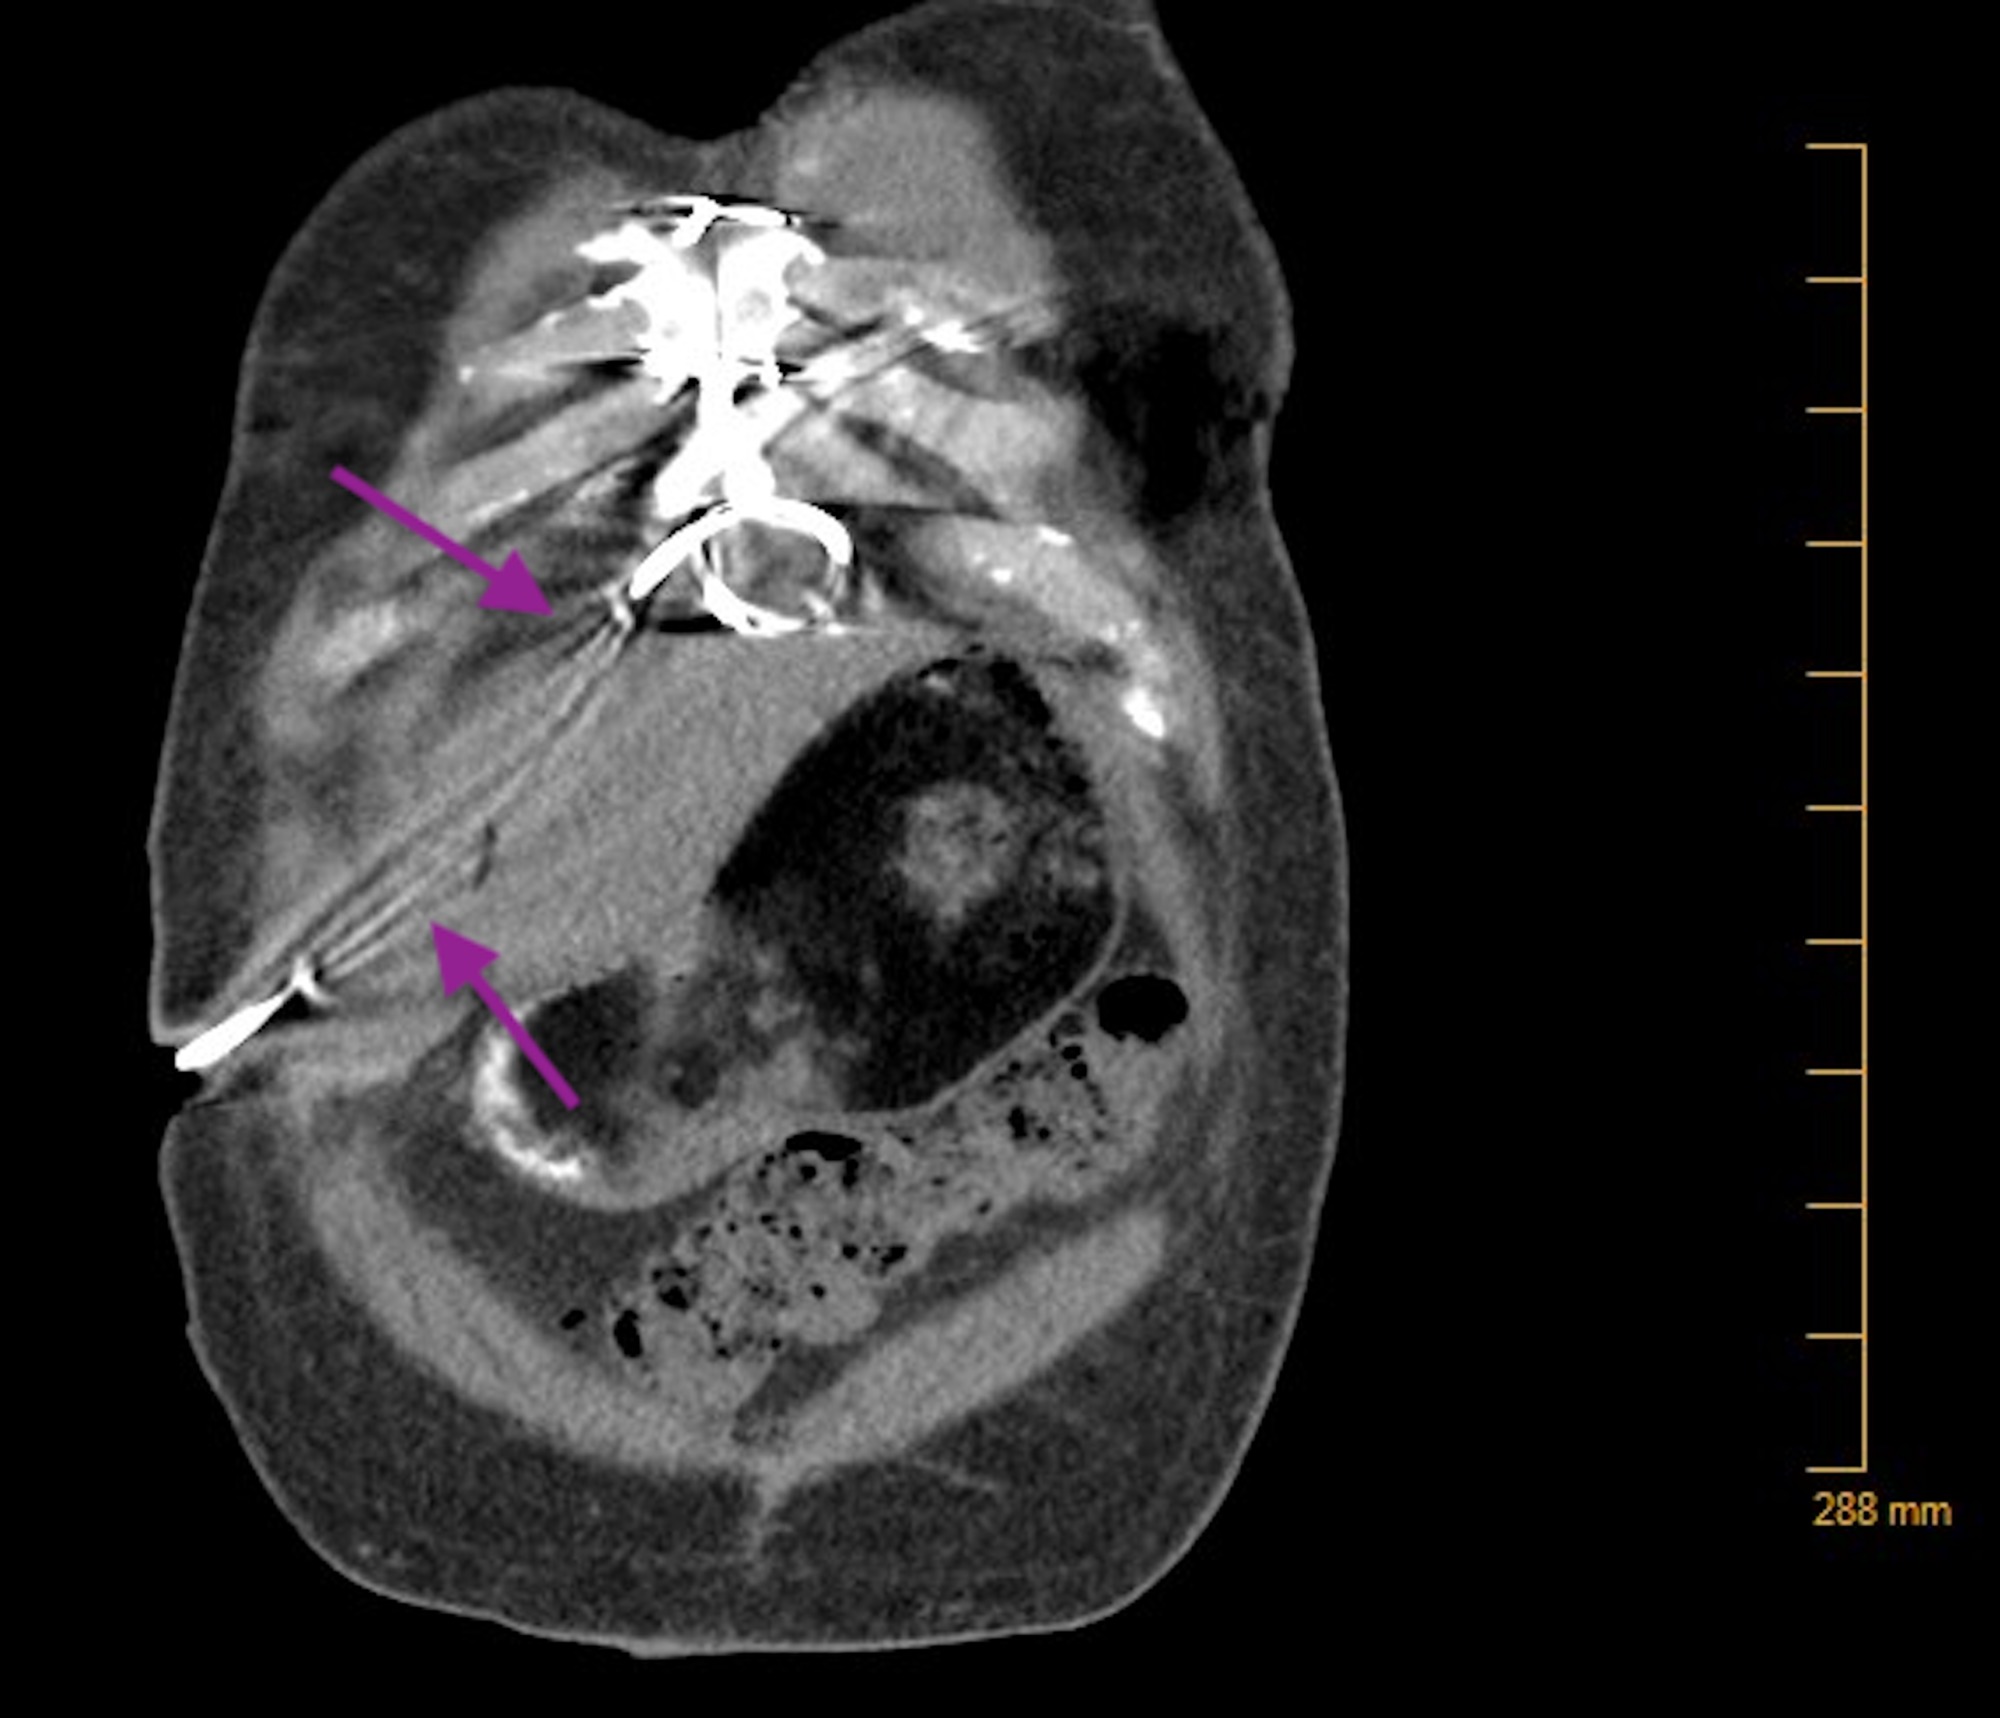

LVAD driveline infection with intrathoracic extension. a CT image shows What Is A Driveline Infection Driveline infections are associated with significant morbidity and mortality. Focus is placed on prevention along every aspect of the process of lvad therapy, as the authors believe this is the most. Infection is the most common complication in patients undergoing ventricular assist device (vad) implantation. Infection is the fourth leading cause of death in lvad patients. A driveline infection refers. What Is A Driveline Infection.

LVAD driveline infection with intrathoracic extension. (a) CT image What Is A Driveline Infection The driveline has a roughened velour material to facilitate adhesion to the subcutaneous tissues along the course of the. 30 the most common site of infection is the driveline, because it is a direct. After implantation of a left ventricular assist device (lvad), driveline infection remains one of the most common complications. As more patients live longer with ventricular assist.. What Is A Driveline Infection.

LVAD driveline infection with intrathoracic extension. a CT image shows What Is A Driveline Infection A driveline infection refers to the most common type of infection in lvad patients, often associated with invasive infections, and. After implantation of a left ventricular assist device (lvad), driveline infection remains one of the most common complications. As more patients live longer with ventricular assist. 30 the most common site of infection is the driveline, because it is a. What Is A Driveline Infection.